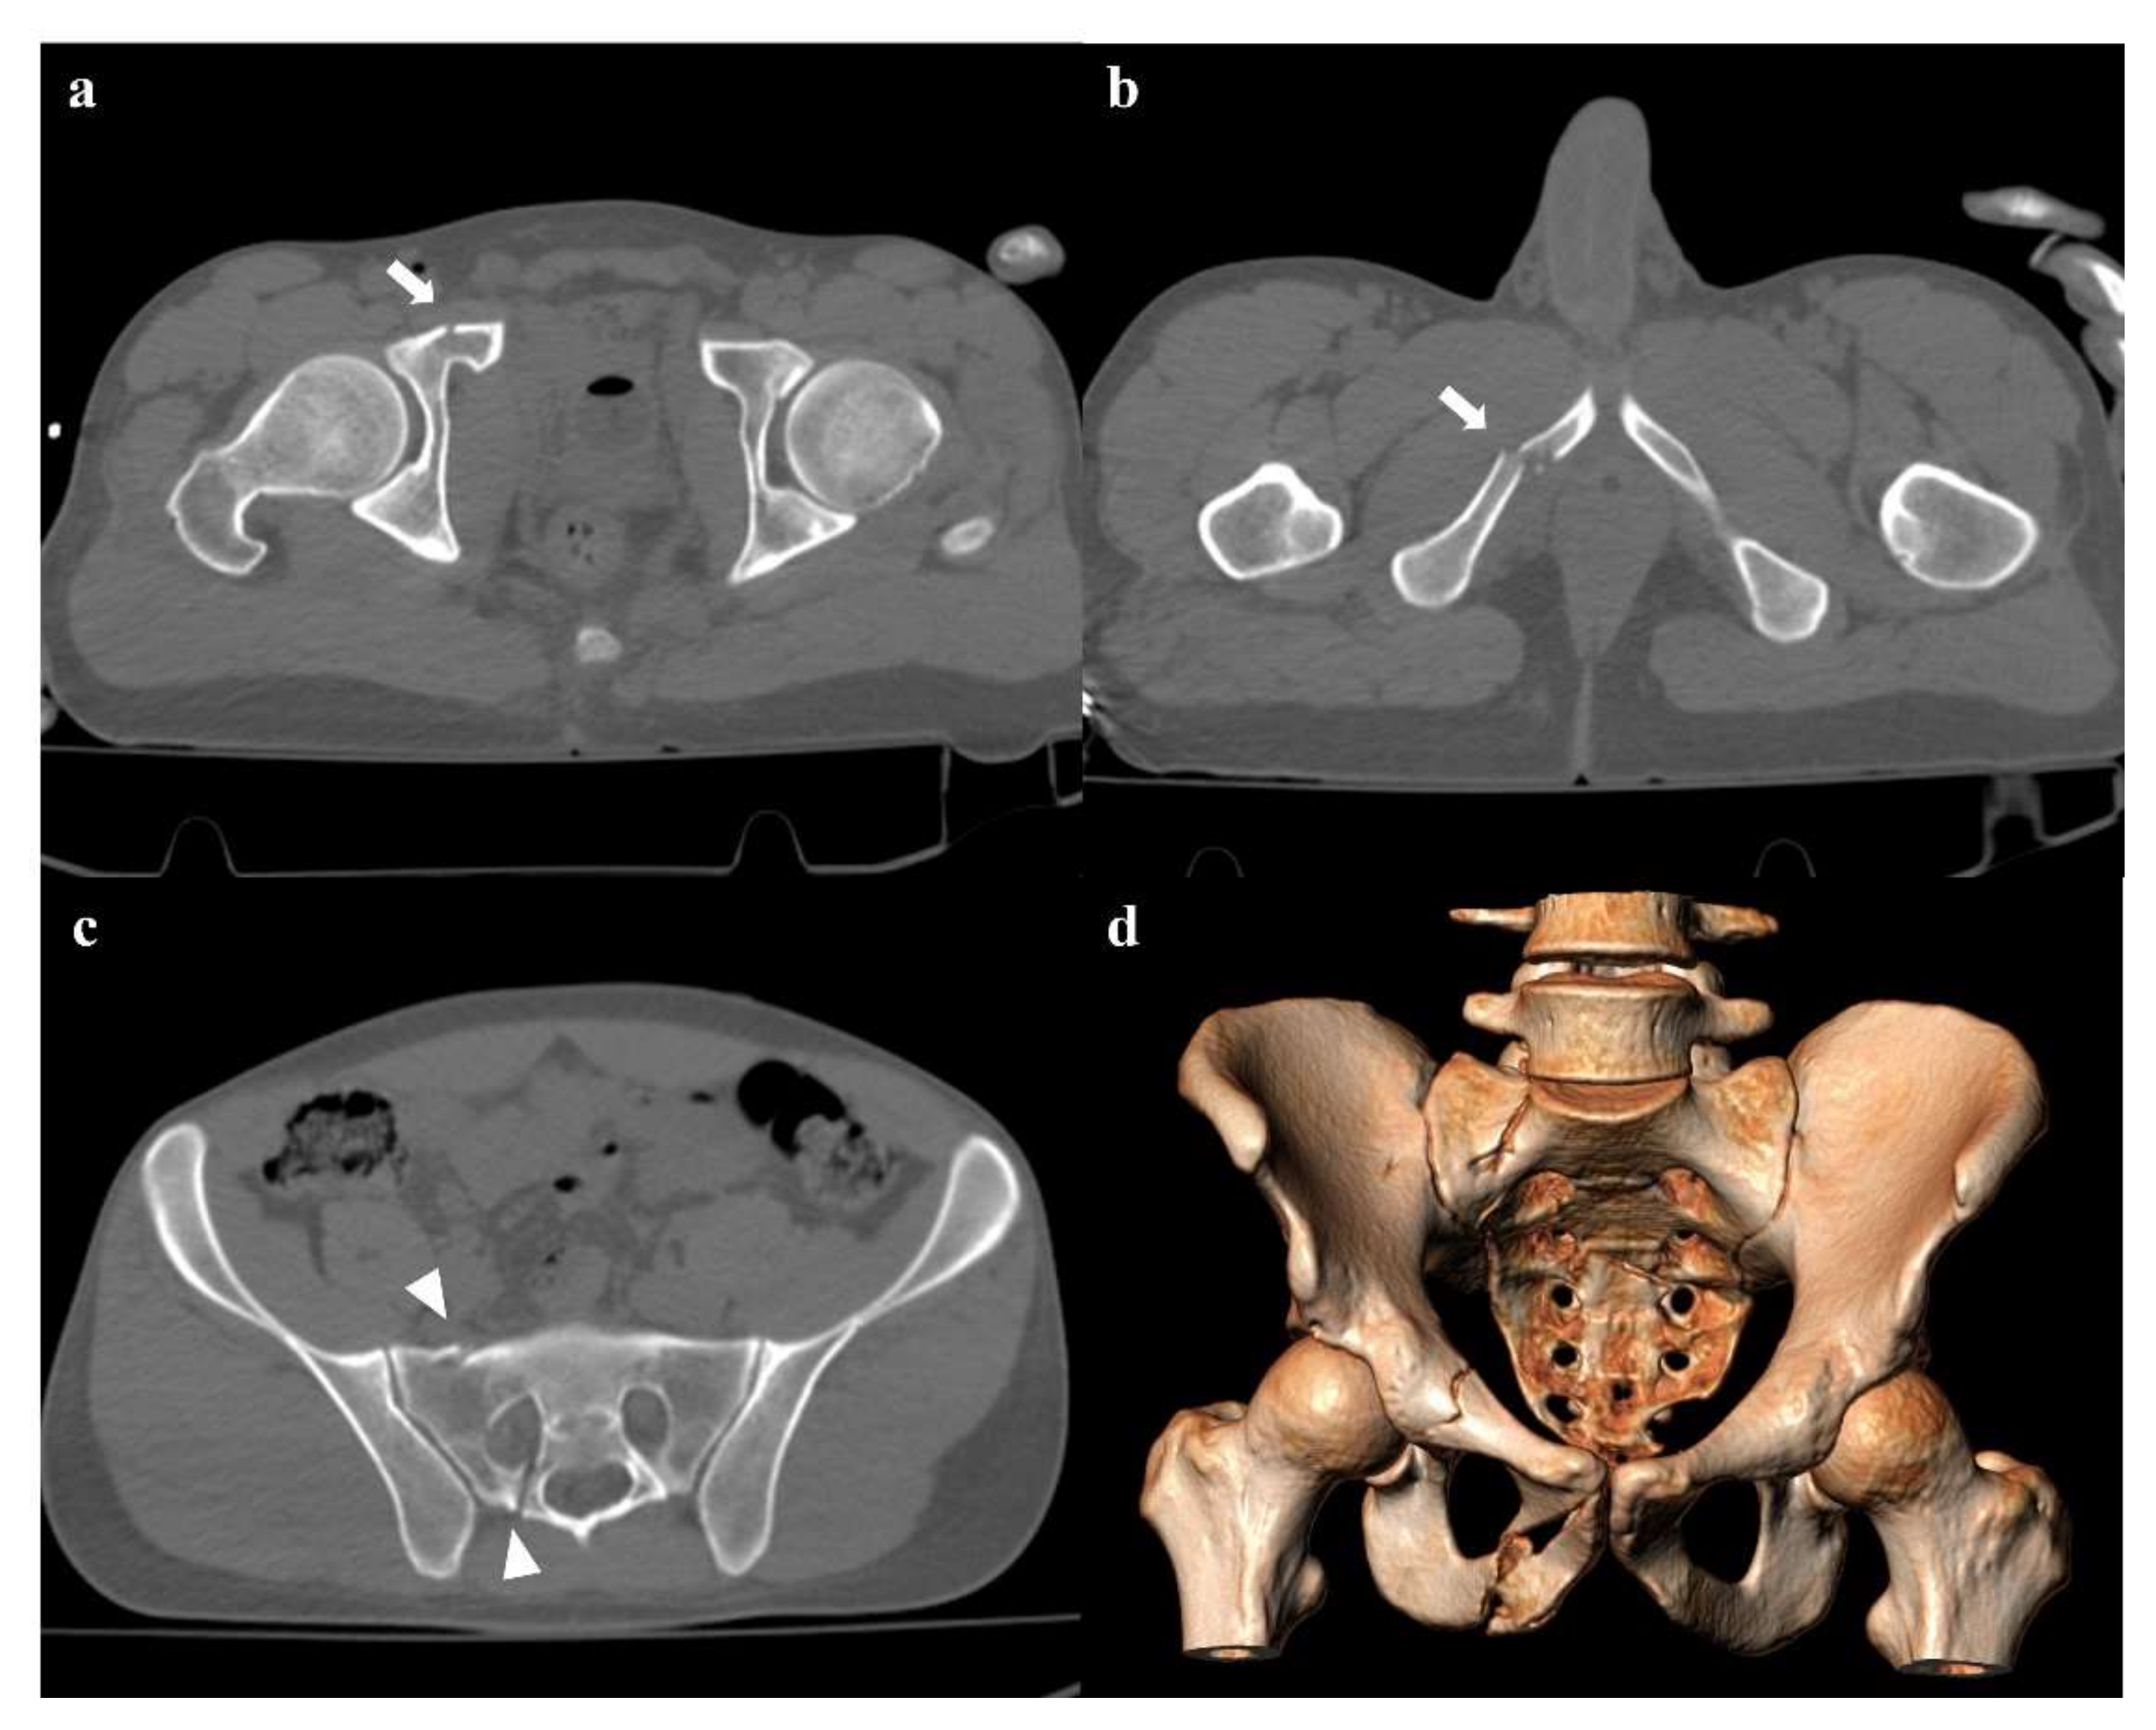

• Grade 2: grade 1 fractures, iliac wing fracture, posterior sacroiliac joint diastasis (Figure 2). Lateral compression grade 2 injuries have a rotational instability and require a stable internal fixation [3]. In these lesions, an adjunctive temporary external fixation is useful [3].

• Zone I: the fracture is located in the sacral wing, lateral to the neuroforamina (Figure 2). In 6% of cases, there is an impingement of L5 or S1 nerve root.

Figure 2. Lateral compression fracture, type 2. Axial CT images show a fracture of both the sacral wings (arrows in (a)), without the involvement of the neuroforamina (zone I). There is also fracture of the iliac wing on the right side (arrow in (b)), and ipsilateral fracture of the superior and inferior pubic branches (arrowheads in (c,d)).